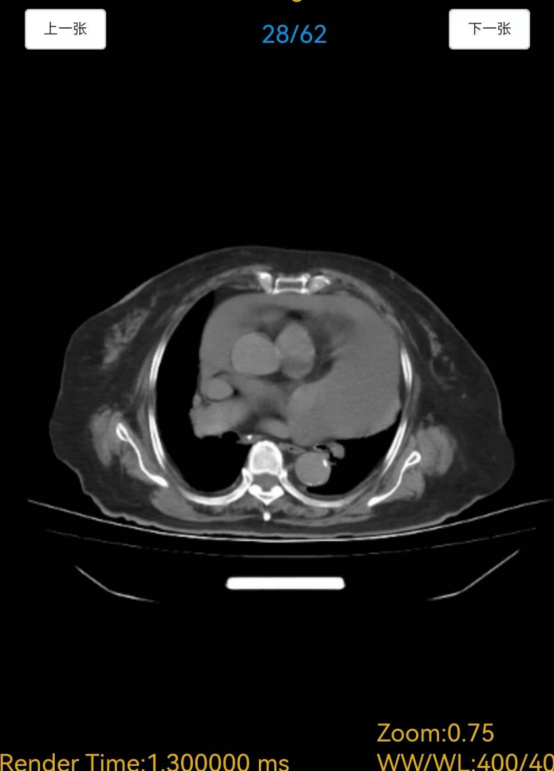

医院骨科徐信龙主任联合麻醉手术科、心内科、呼吸与危重症医学科、老年医学科等专家,开展多学科会诊(MDT),全面、细致地评估王奶奶的身体状况。评估结果不容乐观,一是老人生理机能退化,心肺储备能力差,B超提示心包积液,若不及时处理,可能导致心脏压塞,直接危及生命,而长期卧床又易引发肺部感染、深静脉血栓等严重并发症;二是老人基础病较多,长期服用多种药物,需调整用药方案以避免术中、术后风险;三是术后恢复难题,高龄患者伤口愈合慢,易出现感染、血栓、压疮等并发症。面对“先处理心脏问题还是先解决骨折”的两难局面,骨科、心内科、麻醉手术科等多学科专家共同评估后认为,需先通过心包穿刺引流术解除心脏压迫,待患者生命体征稳定后,再进行人工股骨头置换术。

心内科团队率先行动,王琛主任在超声引导下为患者实施心包穿刺引流术,精准抽出积液,患者胸闷、气促症状明显缓解,心脏功能得到改善。骨科团队针对王奶奶的基础疾病,提前制定输血、抗血栓、感染预防等预案。护理团队指导老人进行呼吸功能锻炼和床上排便训练,做好心理辅导缓解其焦虑情绪。